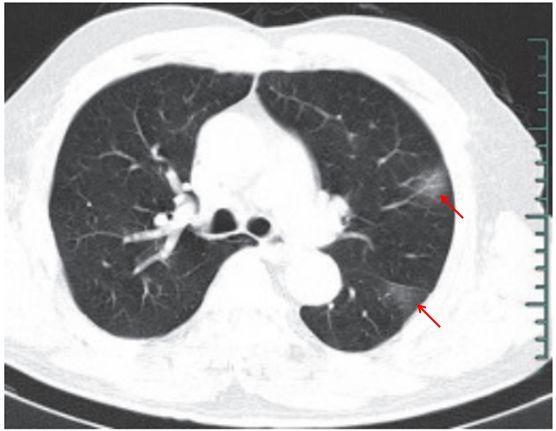

(二)隐球菌感染

肺隐球菌病的病原体为新型隐球菌,此菌为土壤、牛乳、鸽粪和水果等中的腐生菌,感染途径为吸入性。感染人群多见于 40~60岁的成人,临床症状轻,呈亚急性或慢性感染,可侵犯中枢神经系统,表现为慢性脑膜炎、脑膜脑炎或颅内压增高症状。

影像学表现:

(1)呈单发或多发斑片 、 类 圆形 或结 节 影, 多位 于 胸膜下(图 3-11)。

(2)可出现小空洞、晕征,有时呈炎性肿块改变(图 3-12)。

(3)肺门及纵隔淋巴结一般无肿大。

(4)病情进展缓慢。